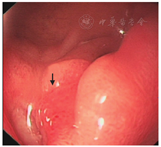

手术次日16: 00患者突发黑便,询问患者无任何不适,精神食欲佳。查体:血压115/80 mmHg,脉搏78次/min,上腹部无压痛及反跳痛。急查大便常规,结果提示潜血弱阳性(±),再次送检,结果提示潜血(+),考虑存在消化道出血可能。立即调整治疗方案:停用雷贝拉唑,改为泮托拉唑注射液40 mg(静脉滴注1次/8 h)+康复新液(10 ml, 3次/d),密切观察病情变化,并急查血常规,结果提示血红细胞3.66×1012/L,血红蛋白108 g/L,与术前对照,发现血红蛋白下降明显(入院时为151 g/L),下降幅度达43 g/L。根据BARC出血分型为3a型[10],属于严重出血,再次询问患者临床,仍无腹痛、腹胀,亦无头晕、出汗,查体发现血压、心率无变化,上腹部仍无压痛及反跳痛,故立即调整双联抗血小板方案。根据我国专家共识,严重出血(如BARC出血分型≥3型)患者应考虑减少药物种类及剂量[11],但对于血栓事件高风险的患者应积极采用内镜下止血治疗,并尽可能保留双联抗血小板药物治疗。结合该患者临床情况,考虑其属于血栓高危患者,主要原因为:患者为非ST段抬高型急性冠状动脉综合征;出血时间为PCI术后24 h;术中曾发生无复流现象,重要的是该患者一旦发生支架内血栓,可能带来严重心血管不良事件。因此最终选择保留双联抗血小板药物治疗,当晚停用阿司匹林1次,将阿司匹林(0.1 g, 1次/晚)直接替换为吲哚布芬(0.1 g,2次/d)。同时禁食,静脉补充营养,将泮托拉唑静脉滴注由1次/8 h改为1次/6 h,同时严密监测患者心率和血压,每天复查血常规及大便常规,准备胃镜检查。复查血红蛋白,第2天为106 g/L,第3天为105 g/L,第4天为108 g/L,维持稳定。连续监测大便常规,大便逐渐成形,颜色由黑变黄,大便常规潜血也逐步变为弱阳性。胃镜检查提示十二指肠球部溃疡,但未见活动性出血(图6)。

| 入院第8天 | 患者行胃镜检查,提示十二指肠球部溃疡,出血已停止。第8天出院,口服双联抗血小板及护胃等药物 |